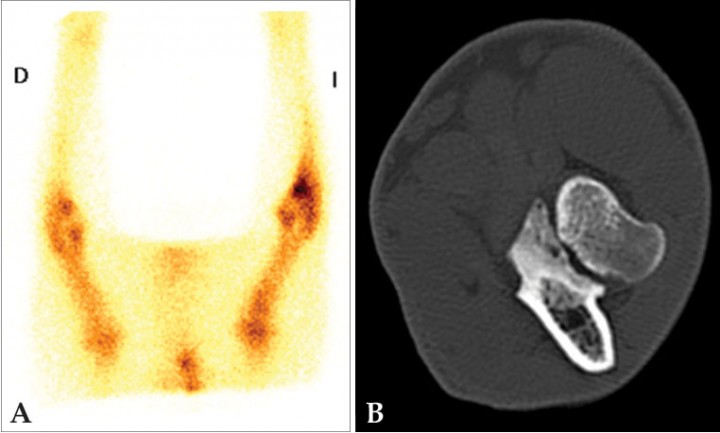

Ocasionalmente, el examen clínico puede no ser concluyente en la localización de la cojera debido a que el paciente presente una gran tolerancia al dolor, ausencia de palpación de anomalías morfológicas o no permita el examen por estrés, agresividad o hiperestesia.[ Schwarz T, Johnson VS, Voute L, Sullivan M. Bone scintigraphy in the investigation of occult lameness in the dog. J Small Anim Pract. 2004; 45(5):232-237. [PubMed] , Samoy Y, Van Ryssen B, Van Caelenberg A et al. Single-phase bone scintigraphy in dogs with obscure lameness. J Small Anim Pract. 2008; 49(9):444-450. [PubMed] ] La radiología puede así mismo no ser concluyente, ya que los cambios radiológicos pueden retrasarse en su aparición o no reflejar la causa de la cojera. La gammagrafía es una técnica muy sensible para detectar cambios tempranos en la remodelación ósea y/o verdadera patología y para evaluar la actividad de la lesión.[ Schwarz T, Johnson VS, Voute L, Sullivan M. Bone scintigraphy in the investigation of occult lameness in the dog. J Small Anim Pract. 2004; 45(5):232-237. [PubMed] , Samoy Y, Van Ryssen B, Van Caelenberg A et al. Single-phase bone scintigraphy in dogs with obscure lameness. J Small Anim Pract. 2008; 49(9):444-450. [PubMed] ] Por ejemplo, en el diagnóstico diferencial de cojeras del miembro anterior permite determinar si la patología tiene su origen en el codo (fragmentación del proceso coronoides medial) o en el hombro (lesiones del sistema extensor o contracturas del músculo infraespinoso/supraespinoso). Al localizar anatómicamente la lesión, es posible restringir a la zona afectada los estudios de tomografía computarizada (TC) o artroscopia (Figs. 11-13).[ Samoy Y, Van Ryssen B, Van Caelenberg A et al. Single-phase bone scintigraphy in dogs with obscure lameness. J Small Anim Pract. 2008; 49(9):444-450. [PubMed] , Van Bruggen LW, Hazewinkel HA, Wolschrijn CF, Voorhout G, Pollak YW, Barthez PY. Bone scintigraphy for the diagnosis of an abnormal medial coronoid process in dogs. Vet Radiol Ultrasound. 2010; 51(3):344-348. [PubMed] , Debruyn K, Peremans K, Vandermeulen E, Van Ryssen B, Saunders JH. Evaluation of semi-quantitative bone scintigraphy in canine elbows. Vet J. 2013; 196(3):424-430. [PubMed] ]

<p>Estudio de un paciente canino con dolor inespecífico en extremidad anterior izquierda. (<strong>A</strong>) Gammagrafía ósea, adquisición en fase ósea 2 horas después de la administración de <sup>99m</sup>Tc-HDP, proyección ventral de las extremidades anteriores en las que se observa un foco con aumento de captación del radioisótopo en la región de la articulación del codo izquierdo, principalmente en la porción distal de la misma. La imagen es compatible con patología del proceso coronoides medial. (<strong>B</strong>) TC del codo izquierdo del mismo paciente, plano transversal en algoritmo hueso en el que se observa un área hipoatenuante en el coronoides medial sin línea de fractura evidente, compatible con condromalacia y enfermedad de coronoides medial sin presencia de fragmentos. La gammagrafía permitió en este caso localizar la articulación con patología (codo) que es la que se examinó con la TC.</p>

Figura 11

Estudio de un paciente canino con dolor inespecífico en extremidad anterior izquierda. (A) Gammagrafía ósea, adquisición en fase ósea 2 horas después de la administración de 99mTc-HDP, proyección ventral de las extremidades anteriores en las que se observa un foco con aumento de captación del radioisótopo en la región de la articulación del codo izquierdo, principalmente en la porción distal de la misma. La imagen es compatible con patología del proceso coronoides medial. (B) TC del codo izquierdo del mismo paciente, plano transversal en algoritmo hueso en el que se observa un área hipoatenuante en el coronoides medial sin línea de fractura evidente, compatible con condromalacia y enfermedad de coronoides medial sin presencia de fragmentos. La gammagrafía permitió en este caso localizar la articulación con patología (codo) que es la que se examinó con la TC.